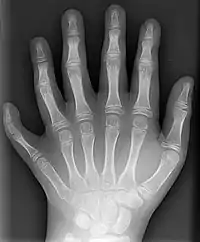

Já no punho, existem oito ossos, referidos conjuntamente como ossos carpais. Tais ossos se organizam em duas fileiras: a fileira proximal (constituída, de lateral para medial, pelos ossos escafoide, semilunar, piramidal e pisiforme); e a fileira distal (formada, também de lateral para medial, por trapézio, trapezoide, capitato e hamato). Trata-se de ossos curtos, que conferem grande flexibilidade ao punho. A fileira proximal dos ossos carpais se articula, em primeiro lugar, com o rádio. Além disso, uma fileira de ossos carpais estabelece articulação com a outra. Por fim, existe articulação entre a fileira distal dos ossos carpais e os ossos metacarapais.[3]

Na sequência, há os ossos que constituem a palma da mão, chamados de ossos metacarpais, numerados de um a cinco.[3] O primeiro osso metacarpal é aquele que se articula com a falange proximal do primeiro dedo (polegar), ao passo que o quinto osso metacarpal é o que estabelece articulação com a falange distal do quinto dedo (mínimo).[9] Apesar do pequeno tamanho, os ossos metacarpais são classificados como ossos longos devido a sua estrutura. Além disso, estabelecem articulação com ossos carpais e falanges proximais.[10]

Enfim, os ossos encontrados nos dedos recebem a nomenclatura de falanges. Em geral, os dedos possuem três falanges: falange proximal (mais próxima da palma da mão), falange média (intermediária) e falange distal (mais distante da palma da mão). No entanto, ainda que os dedos indicador, médio, anelar e mínimo apresentem todos três falanges; o polegar é uma exceção: apresenta somente duas, uma falange proximal e uma falange distal.[3] Assim como os ossos metacarpais, classificam-se como ossos longos, apesar do tamanho, pelo mesmo motivo. As falanges estabelecem articulações entre si e com os ossos metacarpais.[11]

Dessa maneira, cada membro superior apresenta uma escápula, uma clavícula, um úmero, uma ulna, um rádio, oito ossos carpais, cinco ossos metacarpais e quatorze falanges (pois há quatro dedos com três falanges cada uma e um dedo com duas falanges). Isso totaliza 32 ossos em cada membro superior, com 64 ossos ao serem considerados ambos os membros.[3][12] Essa abundância de ossos é consistente com a riqueza de articulações sinoviais ali presentes, responsável pela grande mobilidade, a qual é a principal função dos membros.[7]

Existem, na sequência, junturas entre a fileira distal dos ossos carpais e a base dos ossos metacarpais, denominadas articulações carpometacarpais. No caso do polegar, a junta correspondente é do tipo selar, em que há movimentos de flexão e extensão, adução e adução, circundução e oposição do polegar. Em contrapartida, as demais articulações entre carpo e metacarpo se enquadram como sinovial plana, a qual permite apenas deslizamento.[3][13]

Os ossos metacarpais também apresentam, entre si, pequenas áreas de articulação, para que haja deslizamento entre um e outro durante o movimento de "mão em concha". São sinoviais planas, denominadas articulações intermetacarpais.[3][13]

Em seguida, articulações sinoviais elipsoideas ocorrem entre a cabeça de cada osso metacarpal e a base de sua respectiva falange proximal. São juntas chamadas de articulações metacarpofalângicas, as quais promovem flexão e extensão, adução e abdução, bem como circundução dos dedos. Excepcionalmente, a articulação metacarpofalângica se limita aos movimentos de flexão e extenção, não realiza adução e abdução, funcionando como gínglimo.[3][13]

Em última instância, percebem-se juntas entre a cabeça de uma falange e a base de outra. São articulações do tipo gínglimo, para flexão e extensão. Há duas dessas junturas: uma entre a falange distal e a falange média (articulação interfalângica proximal); outra entre a falange média e a falange distal (articulação interfalângica distal). Vale reiterar que, no polegar, há excepcionalmente duas falanges apenas, uma proximal e outra distal, entre as quais há a articulação interfalângica.[3][13]